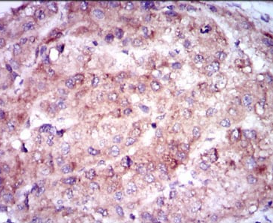

| AC2148 | ENO2 Mouse Monoclonal antibody[5D3B4] | 100ug | $367 | 10days |

| AC2148 | ENO2 Mouse Monoclonal antibody[5D3B4] | 200ug | $660.6 | 10days |